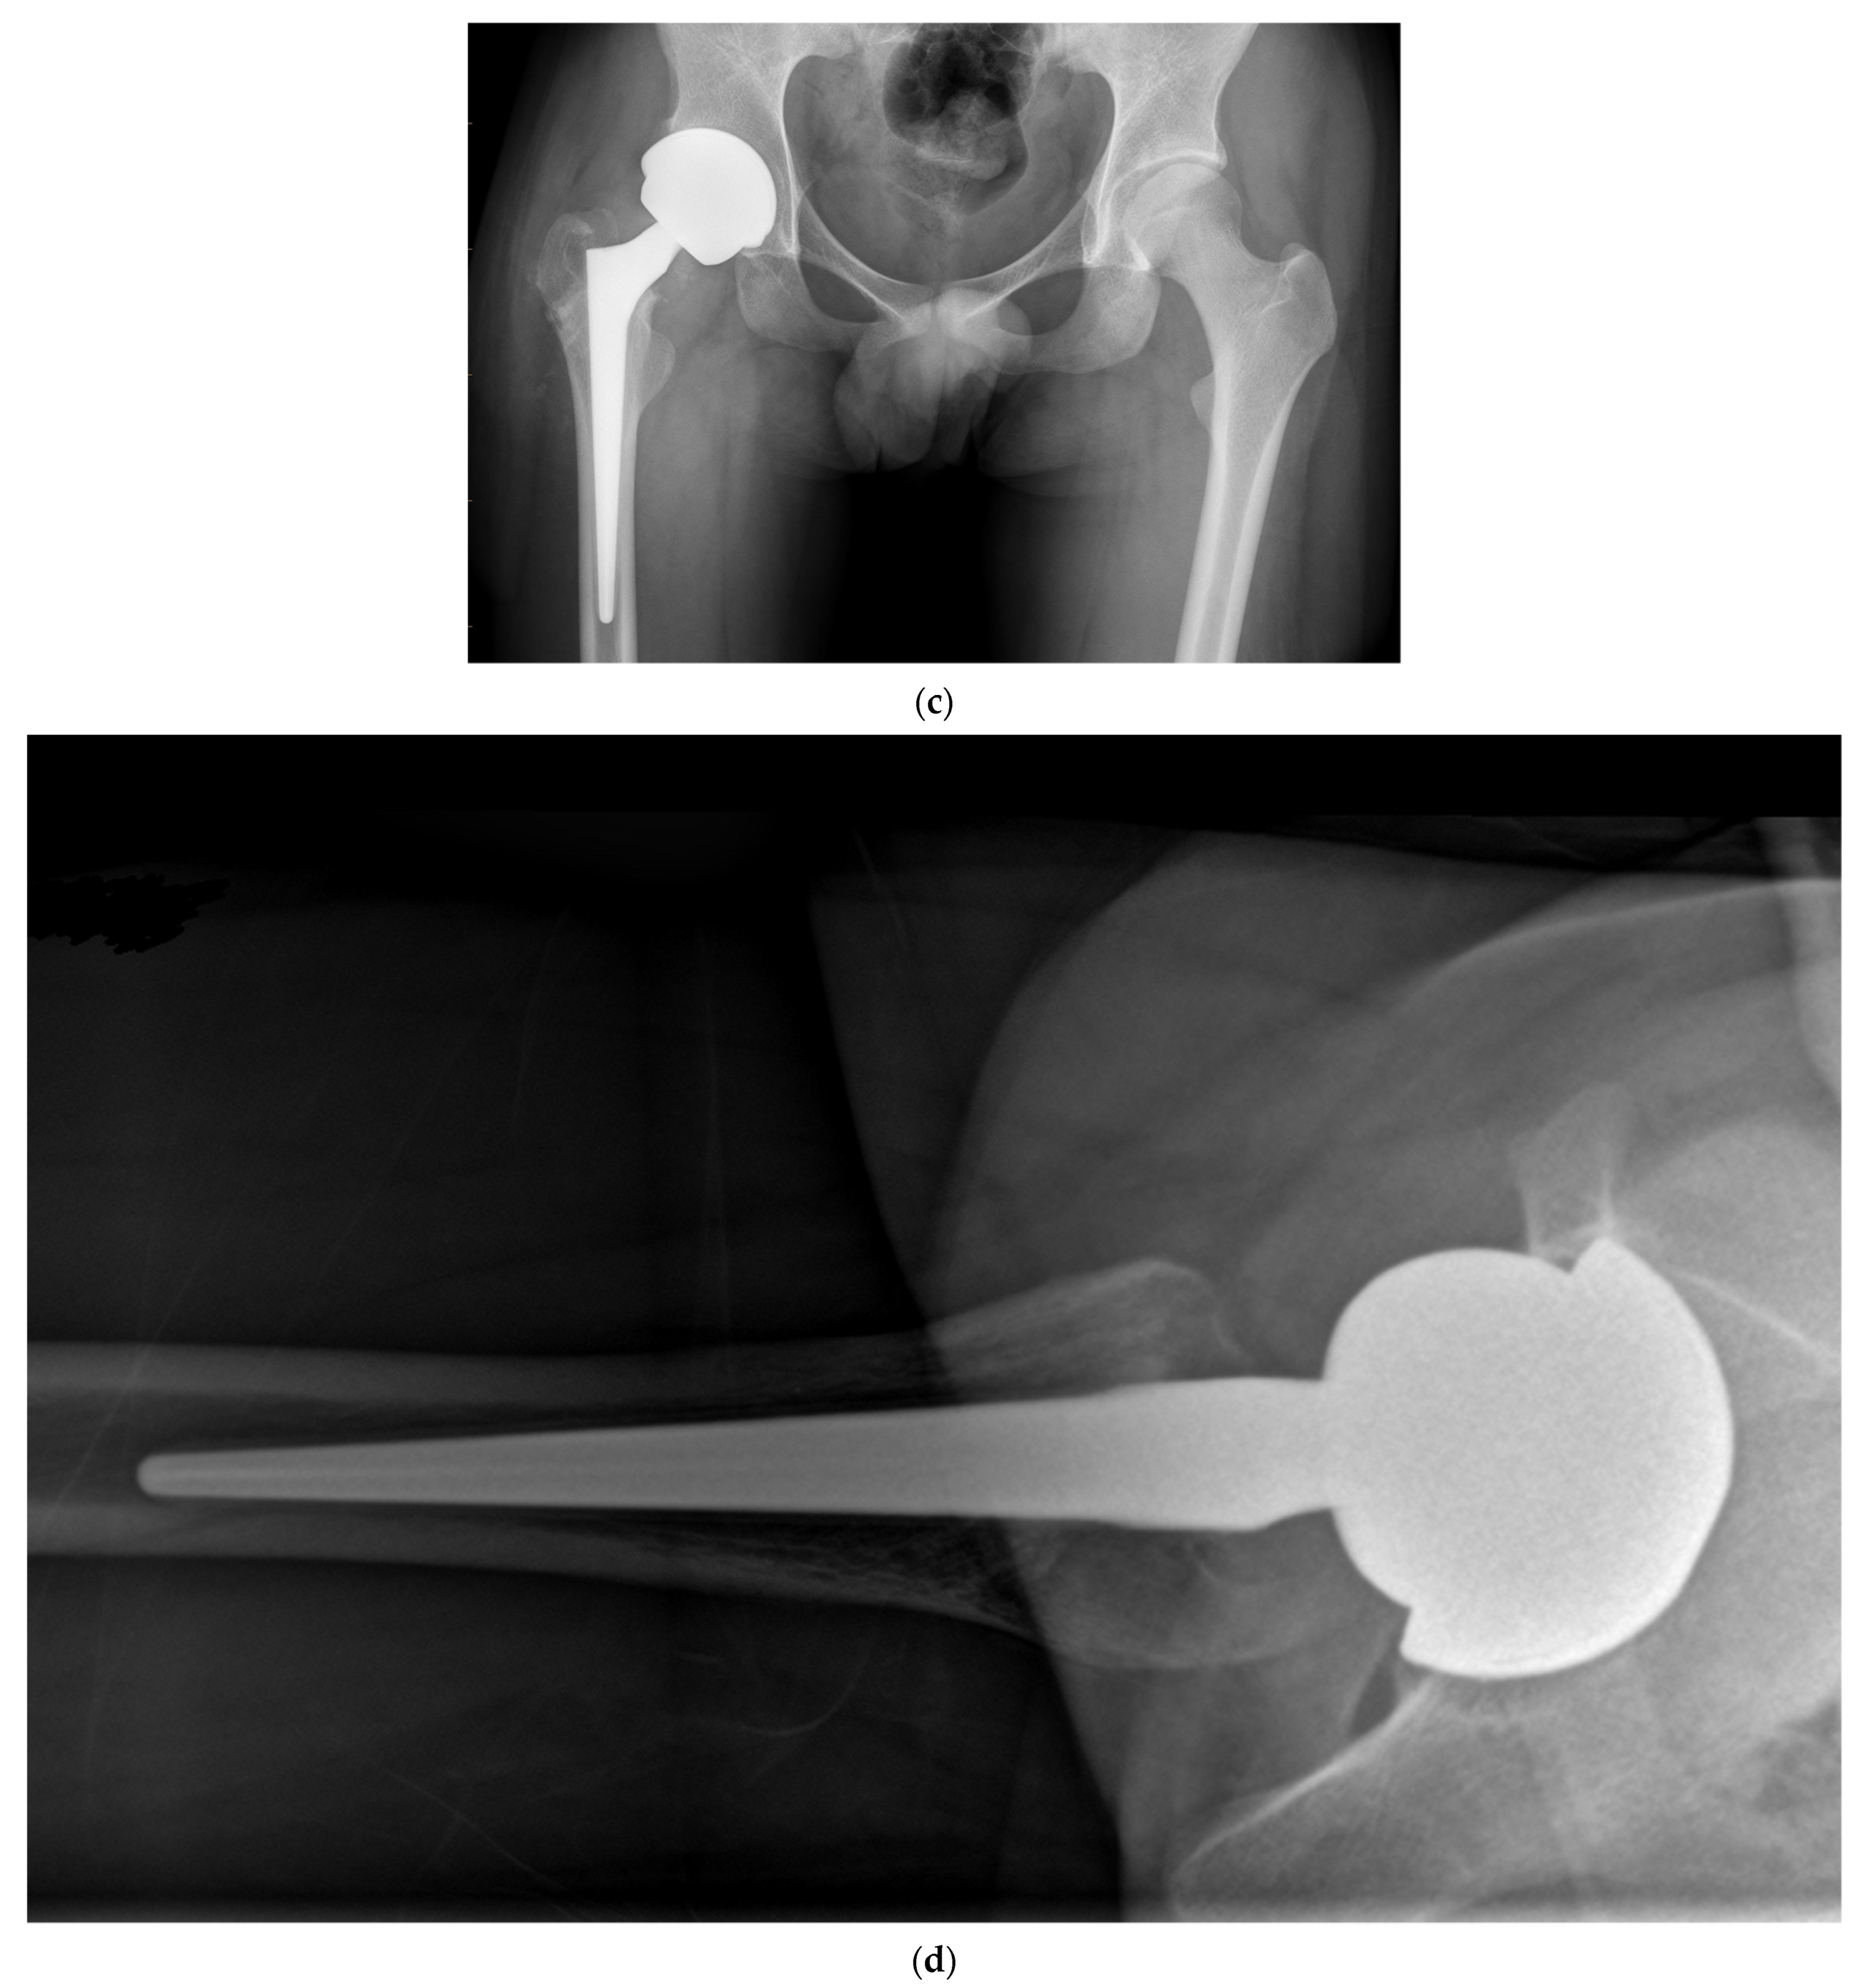

Figure 7.

(a) Antero-posterior pelvis radiograph of a 75-year-old woman with severe bilateral hip osteoarthritis. During the right THA surgery, the acetabular cavity was reamed to 47 mm. A monobloc acetabular component of 48 mm was implanted with a DM polyethylene head of 41 mm (28 mm metal head). A polished tapered stem was cemented. (b) Post-operative anteroposterior pelvis radiograph.